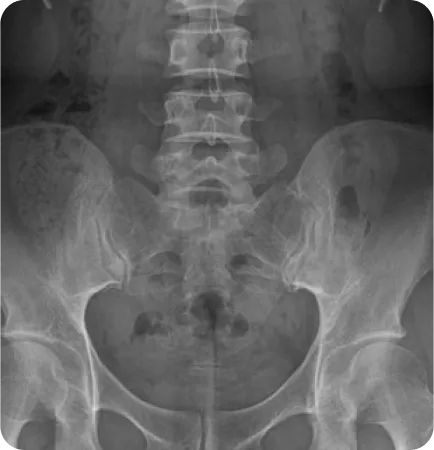

성인의 80%~90%에서 골반 부정렬이 발견되었으며,

그 중 3분의 1은 무증상, 3분의 2는 요통, 골반통 등의 증상을 호소한다.

Wolf Schamberger - The Malalignment Syndrome 中